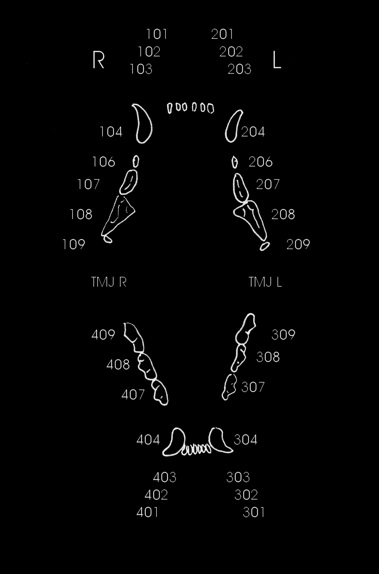

effetti del gioco con le pietre